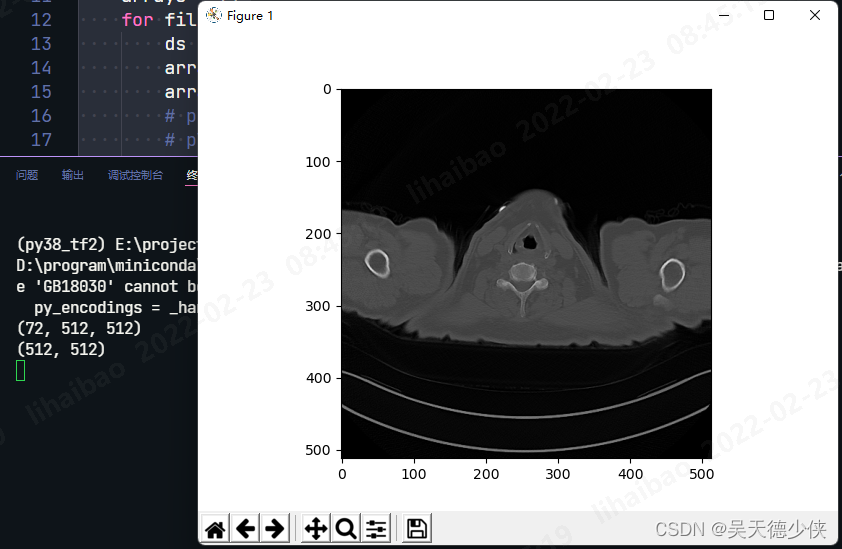

import numpy as npdef extract_voxel_data(files_path_list):arrays = []for file_path in files_path_list:ds = pydicom.dcmread(file_path)array = ds.pixel_arrayarrays.append(array)# print(array.shape)# plt.title(os.path.basename(file_path))# plt.imshow(array,cmap='gray')# plt.show()arrayd = np.dstack(arrays)# 512,512,72 -> 72,512,512arrayd = np.transpose(arrayd,[2,0,1])print(arrayd.shape)return arraydif __name__ == '__main__':workdir = "D:/lung_blood/242/CIUYM10O/PJ1YNRAG"file_names = os.listdir(workdir) # 很多DCM文件序列名# 删掉VERSIONfor file_name in file_names:if file_name == 'VERSION':file_names.remove('VERSION')file_names.sort(key=lambda x: int(x[-7:])) # 按文件顺序排序files_path_list = [os.path.join(workdir,file_name) for file_name in file_names]voxel_ndarry = extract_voxel_data(files_path_list)aimg = voxel_ndarry[0]print(aimg.shape)plt.imshow(aimg,cmap='gray')plt.show()